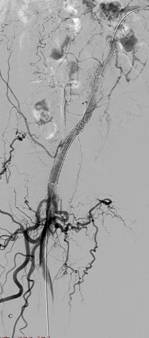

图3 患者男,80岁,间歇性跛行半年,加重伴右下肢疼痛1个月,入院诊断:右下肢动脉硬化闭塞症(ASO)。图A血管造影发现右侧髂总动脉及股总动脉完全闭塞,图B显示用导管导丝技术打开右侧髂总和股总动脉,股深动脉通畅,图C显示右侧髂总动脉及股总动脉放置支架后通畅,右侧股深动脉完全显影,股浅动脉显影。